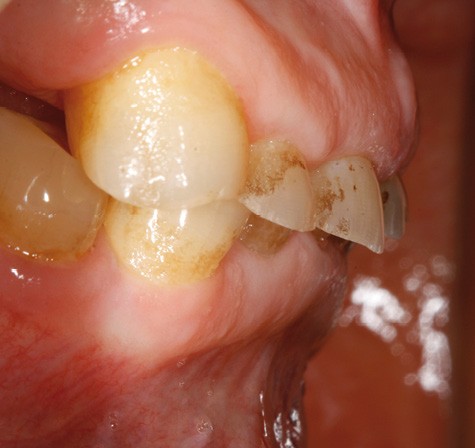

• L’examen intrabuccal montre de nombreux édentements non compensés (14, 15, 16, 24, 25, 26, 27, 47 et 36) ainsi que des pertes de substance très importantes, notamment dans le secteur antérieur.

– perte de substance extrême du bloc incisivo-canin maxillaire et des incisives mandibulaires ;